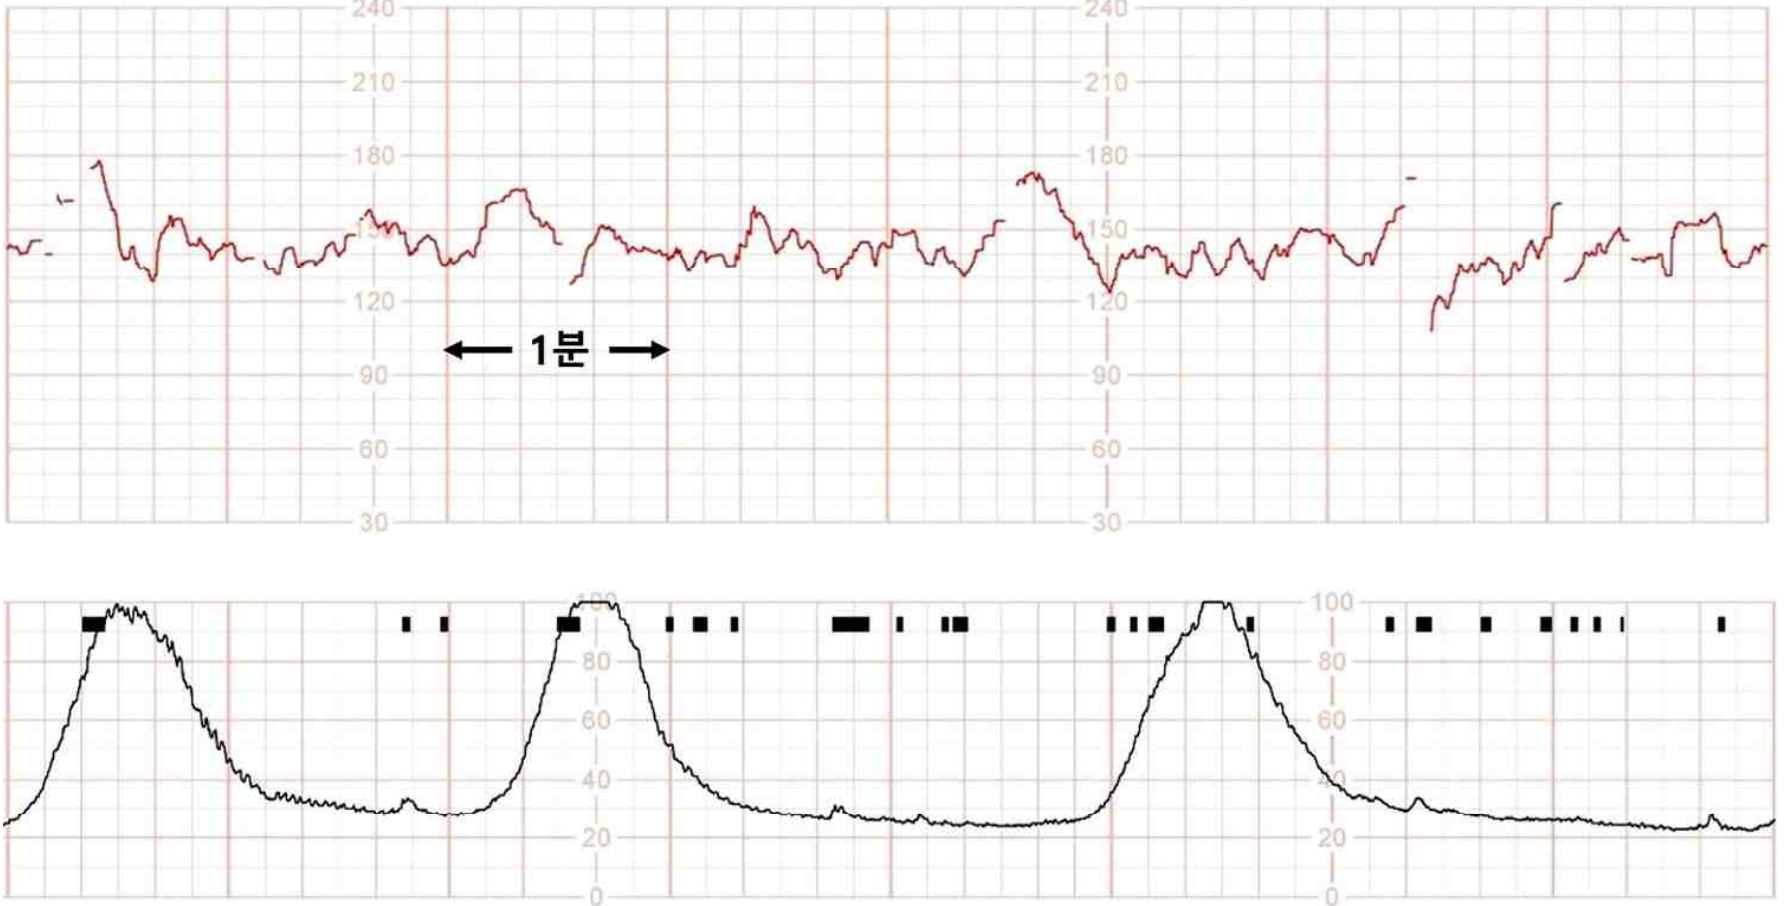

Fetal CTG: FHR nl, uterine contraction, q2-3m

Imp: 조기 진통(preterm labor)

• 산모가 하복부 불편감을 호소할 경우 분만 진통을 의심해야 한다. 자궁경부 개대에 대한 소견은 주어지지 않았지만 fetal CTG상 자궁수축이 규칙적으로 확인되므로 조기 진통이 의심된다.

• 조기 진통 산모에게서 만일 양막파수가 동반되었다면 분만을 그대로 지속해야 하나, 양막파수가 발생하지 않았다면 산모/태아에게 특별한 이상이 없는 한 조속히 분만을 이행해야 할 이유가 없다.

• 현재 산모와 태아는 초음파상 placenta previa외에 특이사항이 확인되지 않으므로 조속한 분만이 필요하지 않다고 판단된다. 따라서 태아 폐성숙을 촉진하기 위한 corticosteroid 투여 시간을 확보하기 위해 자궁수축억제제(tocolytic)를 사용할 수 있다.

• 현재 산모는 fetal CTG에서 MVU>200 이상의 충분한 규칙적 자궁수축이 확인되는데, 본 증례와 같이 조기진통이 강하게 의심되는 상황에서는 임상의사의 적절한 판단 하에 corticosteroid 투여 시간 확보를 위해 자궁수축억제제(tocolytic) 투여가 가능하다고 판단된다.